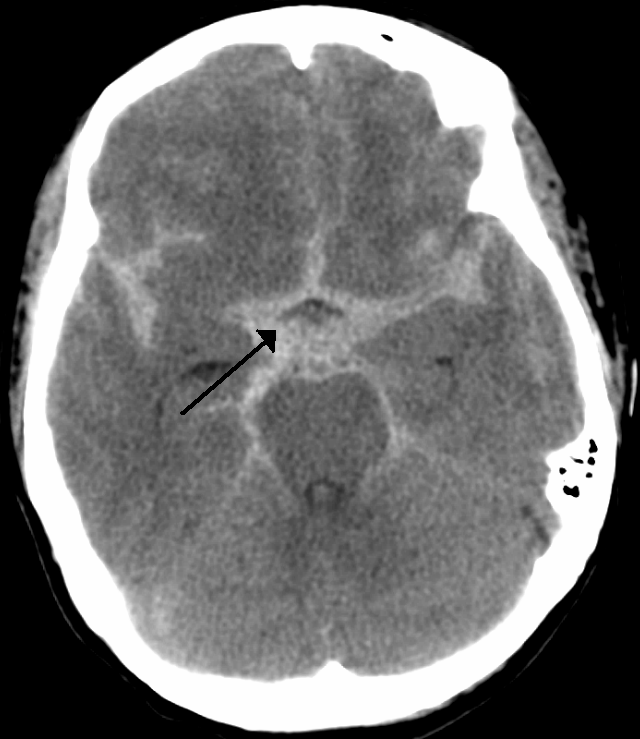

그녀의 최초 촬영한 뇌 CT 영상을 통한 진단명은 대뇌의 거미막하출혈.

(뇌 CT상 별모양의 출혈 양상을 보인다. 일단 거미막하출혈이 발생하면 1/3은 즉사, 1/3은 병원 도착 후 사망, 1/3은 회복한다. https://recapem.com/

거미막하출혈은 두개내 혈관의 파열에 의해 거미막하강내로 출혈되는 것으로 가장 흔한 원인은 외상이고, 비외상성 거미막하출혈의 80%는 뇌동맥류의 파열에 의한 것이다. 또한, 비외상성 거미막하출혈은 병원 전 심정지의 신경학적 원인 중 가장 많은 원인이기도 하다.